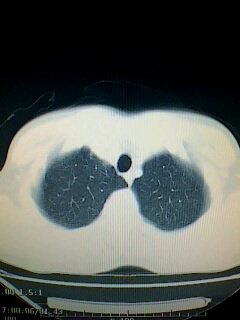

标题: CT28315:咳嗽咳痰咯血半月并胸痛 [打印本页]

标题: CT28315:咳嗽咳痰咯血半月并胸痛

左下肺肿块影,深分叶,考虑肺癌。

左下肺球形病灶,考虑:1:球形肺炎;2:周围型肺癌不除外,建议治疗后复查

不排除左肺下叶周围型肺癌可能!建议穿刺活检!

考虑左肺下叶周围型肺癌并阻塞性肺炎。